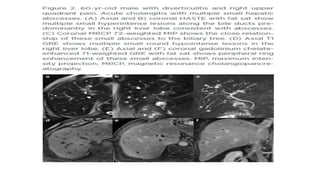

• IgG4-Related Sclerosing Cholangitis

• Immunoglobulin G4-SC is bile duct involvement of IgG4- related systemic disease (IgG4-RD) .

After the pancreas, bile ducts are the second most common organ, involved with IgG4-RD.

Patients with IgG4-SC are predominantly males in their 60s (mean age, 63 years) . Patients

with IgG4-SC commonly present with obstructive jaundice. Like other IgG4-related diseases,

the serum IgG4 is frequently elevated.

• Abdominal US has limited value for diagnosing IgG4- SC, although it may show thickening of

the bile duct and gallbladder. In cases of IgG4-SC, cross-sectional imaging, such as CT or MR

imaging, demonstrates long-segmental, symmetrical, circumferential wall thickening and

delayed contrast enhancement of the involved bile ducts

• Differentiation of IgG4-SC from other types of sclerosing cholangitis, especially from PSC, is

clinically important as IgG4-SC shows a dramatic response to steroid therapy . Patients with

PSC are generally younger and less symptomatic than those with IgG4-related disease .